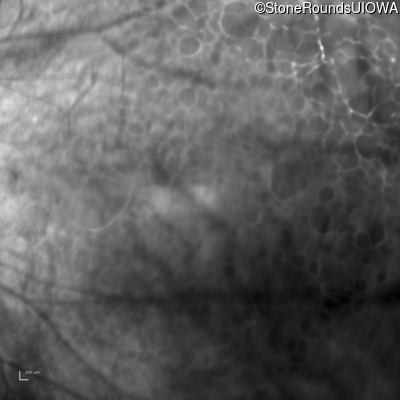

Infrared Fundus Photograph - Right - 20/100 -1

Exemplar

Infrared Fundus Photograph - Left - 20/50 +3